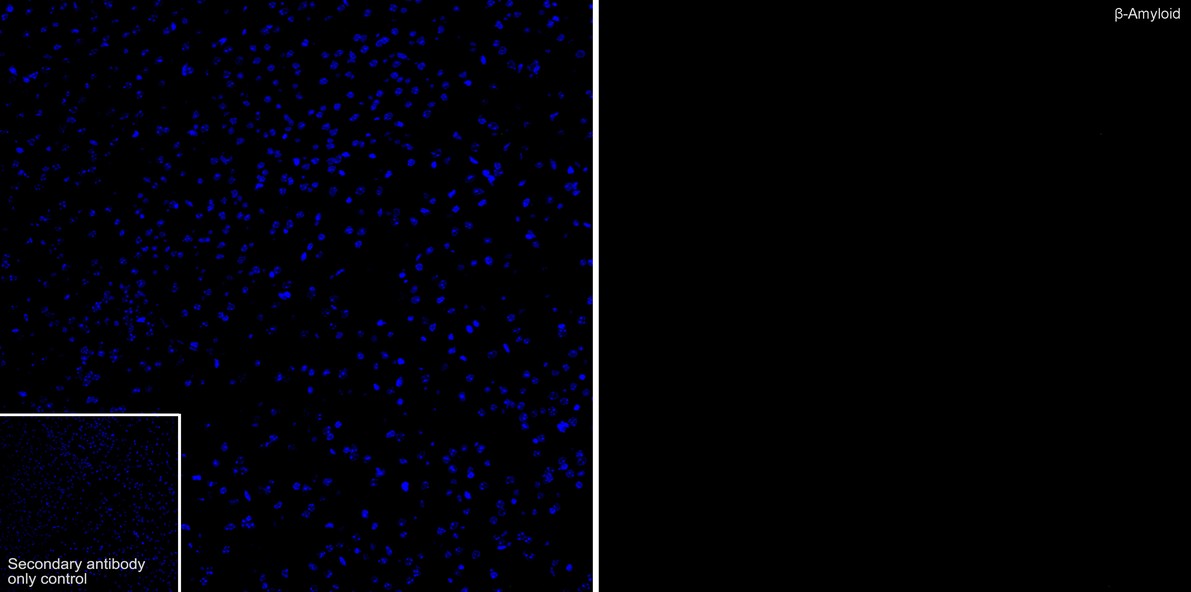

beta Amyloid Recombinant Rabbit Monoclonal Antibody - BSA and Azide free [PSH08-19] (HA751210)

Rabbit Monoclonal to beta Amyloid

IF-Tissue